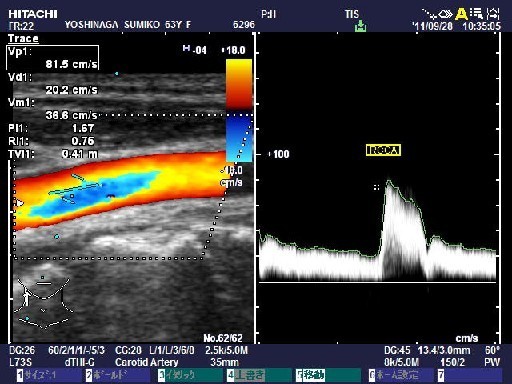

・頸部血管エコー

頚部の血管を超音波で観察することにより、脳動脈の硬化と血流を計測します。

¥4,200